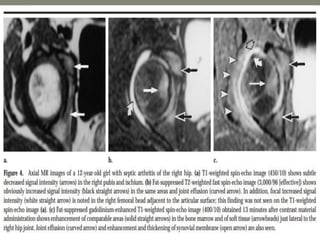

MRI-

1]septic arthritis show signal intensity alteration in the

bone marrow of affected hip joint

2] In transient synovities cases show no such altered

signal entity in bone marrow

T1- poorly defined low signal intesity

T2-/STIR: hyperintese

Contrast study : show enhancment